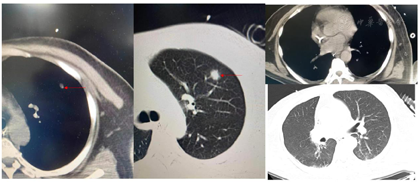

2021年10月28日于青岛大学附属医院行腹部CT(图1)提示肝硬化、脾大、门脉高压、腹水表现、胆囊区高密度影。2021年10月28日胸部CT(图2)提示左肺上叶炎性结节可能,双肺坠积性炎症可能性大,双侧胸膜增厚,右侧少量胸腔积液、心腔密度减低。

患者经口气管插管后给予床旁纤维支气管镜及肺泡灌洗等检查,并留取相关培养。肺泡灌洗液及痰培养结果为肺炎克雷伯菌肺炎亚种、嗜麦芽窄食单胞菌、少动鞘氨醇单胞菌、铜绿假单胞菌、耐甲氧西林金黄色葡萄球菌(Methicillin-resistant Staphylococcus aureus,MRSA)。肺泡灌洗液二代测序技术(又称高通量测序技术,Next Generation Sequencing Technology,NGS)检查:肺炎克雷伯菌、嗜麦芽窄食单胞菌、屎肠球菌、表皮葡萄球菌、EB病毒、巨细胞病毒。血培养为表皮葡萄球菌和摩根菌摩根亚种。尿培养示摩根菌摩根亚种。真菌GM试验2.98S/CO(正常<0.5),真菌G试验1050.2 pg/ml(>151.5阳性)。巨细胞病毒DNA 2.02E+03拷贝/ml(阳性,正常≤5.00E+02)。2021年11月5日行胸部CT检查提示双侧胸腔积液伴双肺下叶萎缩不张,左肺上叶结节,双肺坠积性炎症改变(图7)。

后根据患者感染情况,经医院抗菌管理组会诊,先后给予美罗培南、多黏菌素(静脉联合雾化)、卡泊芬净、伏立康唑、头孢哌酮舒巴坦、替加环素、替考拉宁、两性霉素B雾化、更昔洛韦等积极抗感染治疗。经过积极抗感染、营养支持等相关治疗后,2021年11月16日复查胸部CT提示肺部炎症较前明显好转,见图8。